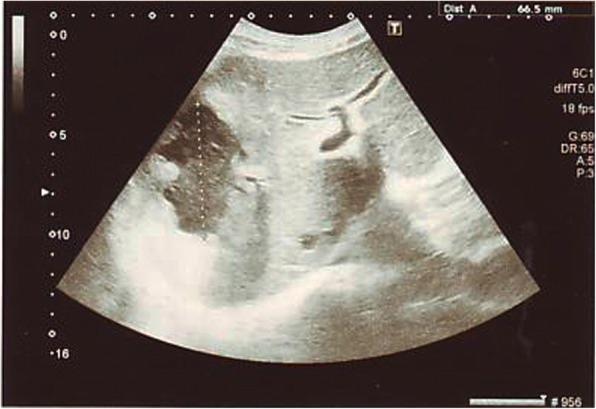

A 63-year-old Sinhalese man with diabetes mellitus and a poor glycemic control presented with fever, loose stools, and loss of appetite of 1 week's duration. An examination was unremarkable apart from a mild non-tender hepatomegaly. Investigations indicated a septic process with neutrophil leukocytosis, thrombocytopenia, and raised inflammatory markers with acute kidney injury. Sonography of his abdomen revealed a large liver abscess with two blood cultures positive for Klebsiella pneumoniae. He made a complete recovery following aspiration of the abscess and treatment with intravenously administered ceftriaxone.

一名63岁的僧伽罗男性,患有糖尿病且血糖控制不佳,出现发热、腹泻和食欲减退1周。检查除轻度无压痛性肝肿大外无异常。检查显示为脓毒症过程,伴有中性粒细胞增多、血小板减少以及炎症标志物升高和急性肾损伤。腹部超声检查发现一个大的肝脓肿,两次血培养肺炎克雷伯菌呈阳性。经脓肿穿刺抽吸及静脉注射头孢曲松治疗后,他完全康复。